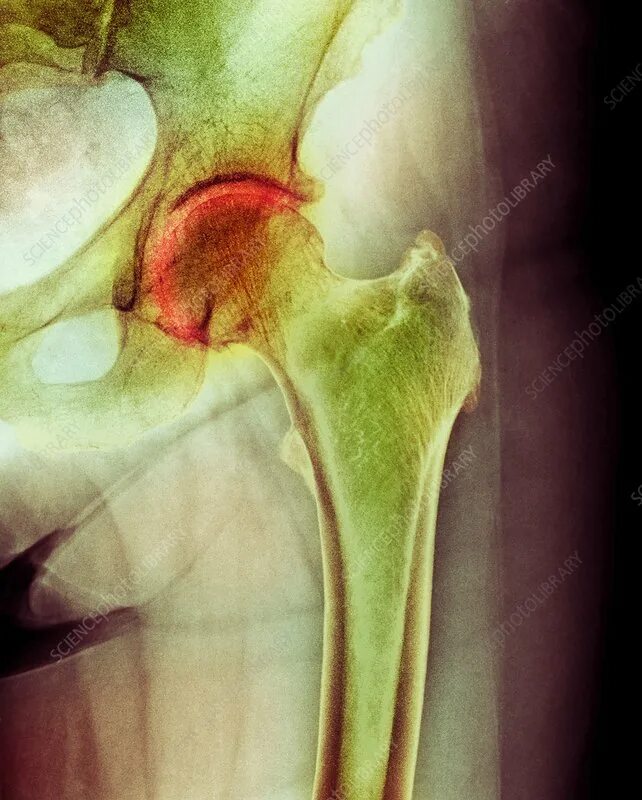

Инвалидность при некрозе тазобедренного сустава